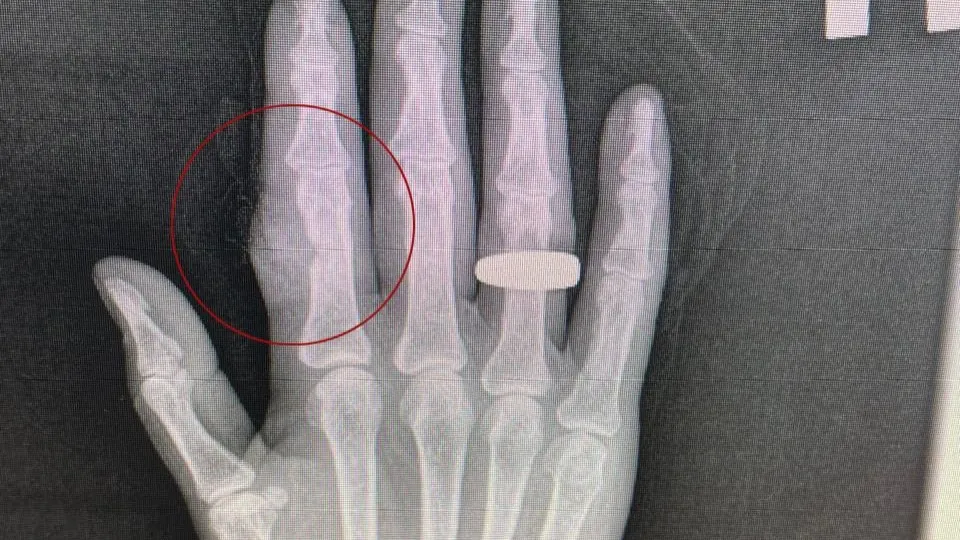

Фото: пресс-служба ступинской больницы

Жительница Ступина раздробила палец циркулярной пилой